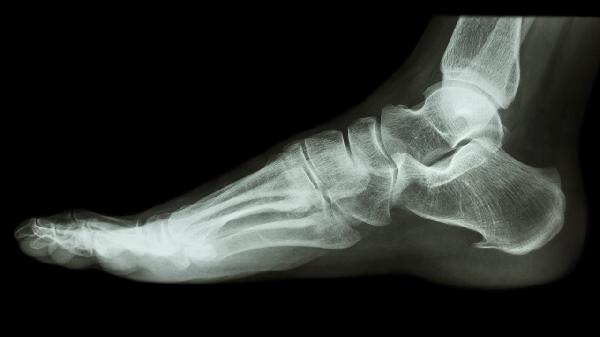

足跟骨质增生可遵医嘱使用布洛芬缓释胶囊、塞来昔布胶囊、硫酸氨基葡萄糖胶囊、双氯芬酸钠缓释片、玻璃酸钠注射液等药物。足跟骨质增生可能与慢性劳损、退行性变、炎症刺激等因素有关,通常表现为足跟疼痛、活动受限等症状。建议及时就医,在医生指导下规范用药。

双氯芬酸钠缓释片具有强效抗炎镇痛作用,适用于骨质增生急性发作期的足跟剧痛。该药对跟骨骨刺压迫周围软组织引发的炎症效果明显,但肝肾功能不全者应调整剂量,服药期间禁止饮酒。

足跟骨质增生患者日常应选择软底缓冲鞋,避免长时间站立或行走。控制体重可减少足部负荷,疼痛期可进行温水泡脚和局部热敷。补钙和维生素D有助于骨骼健康,但需在医生指导下结合药物与康复锻炼综合治疗,定期复查评估病情进展。